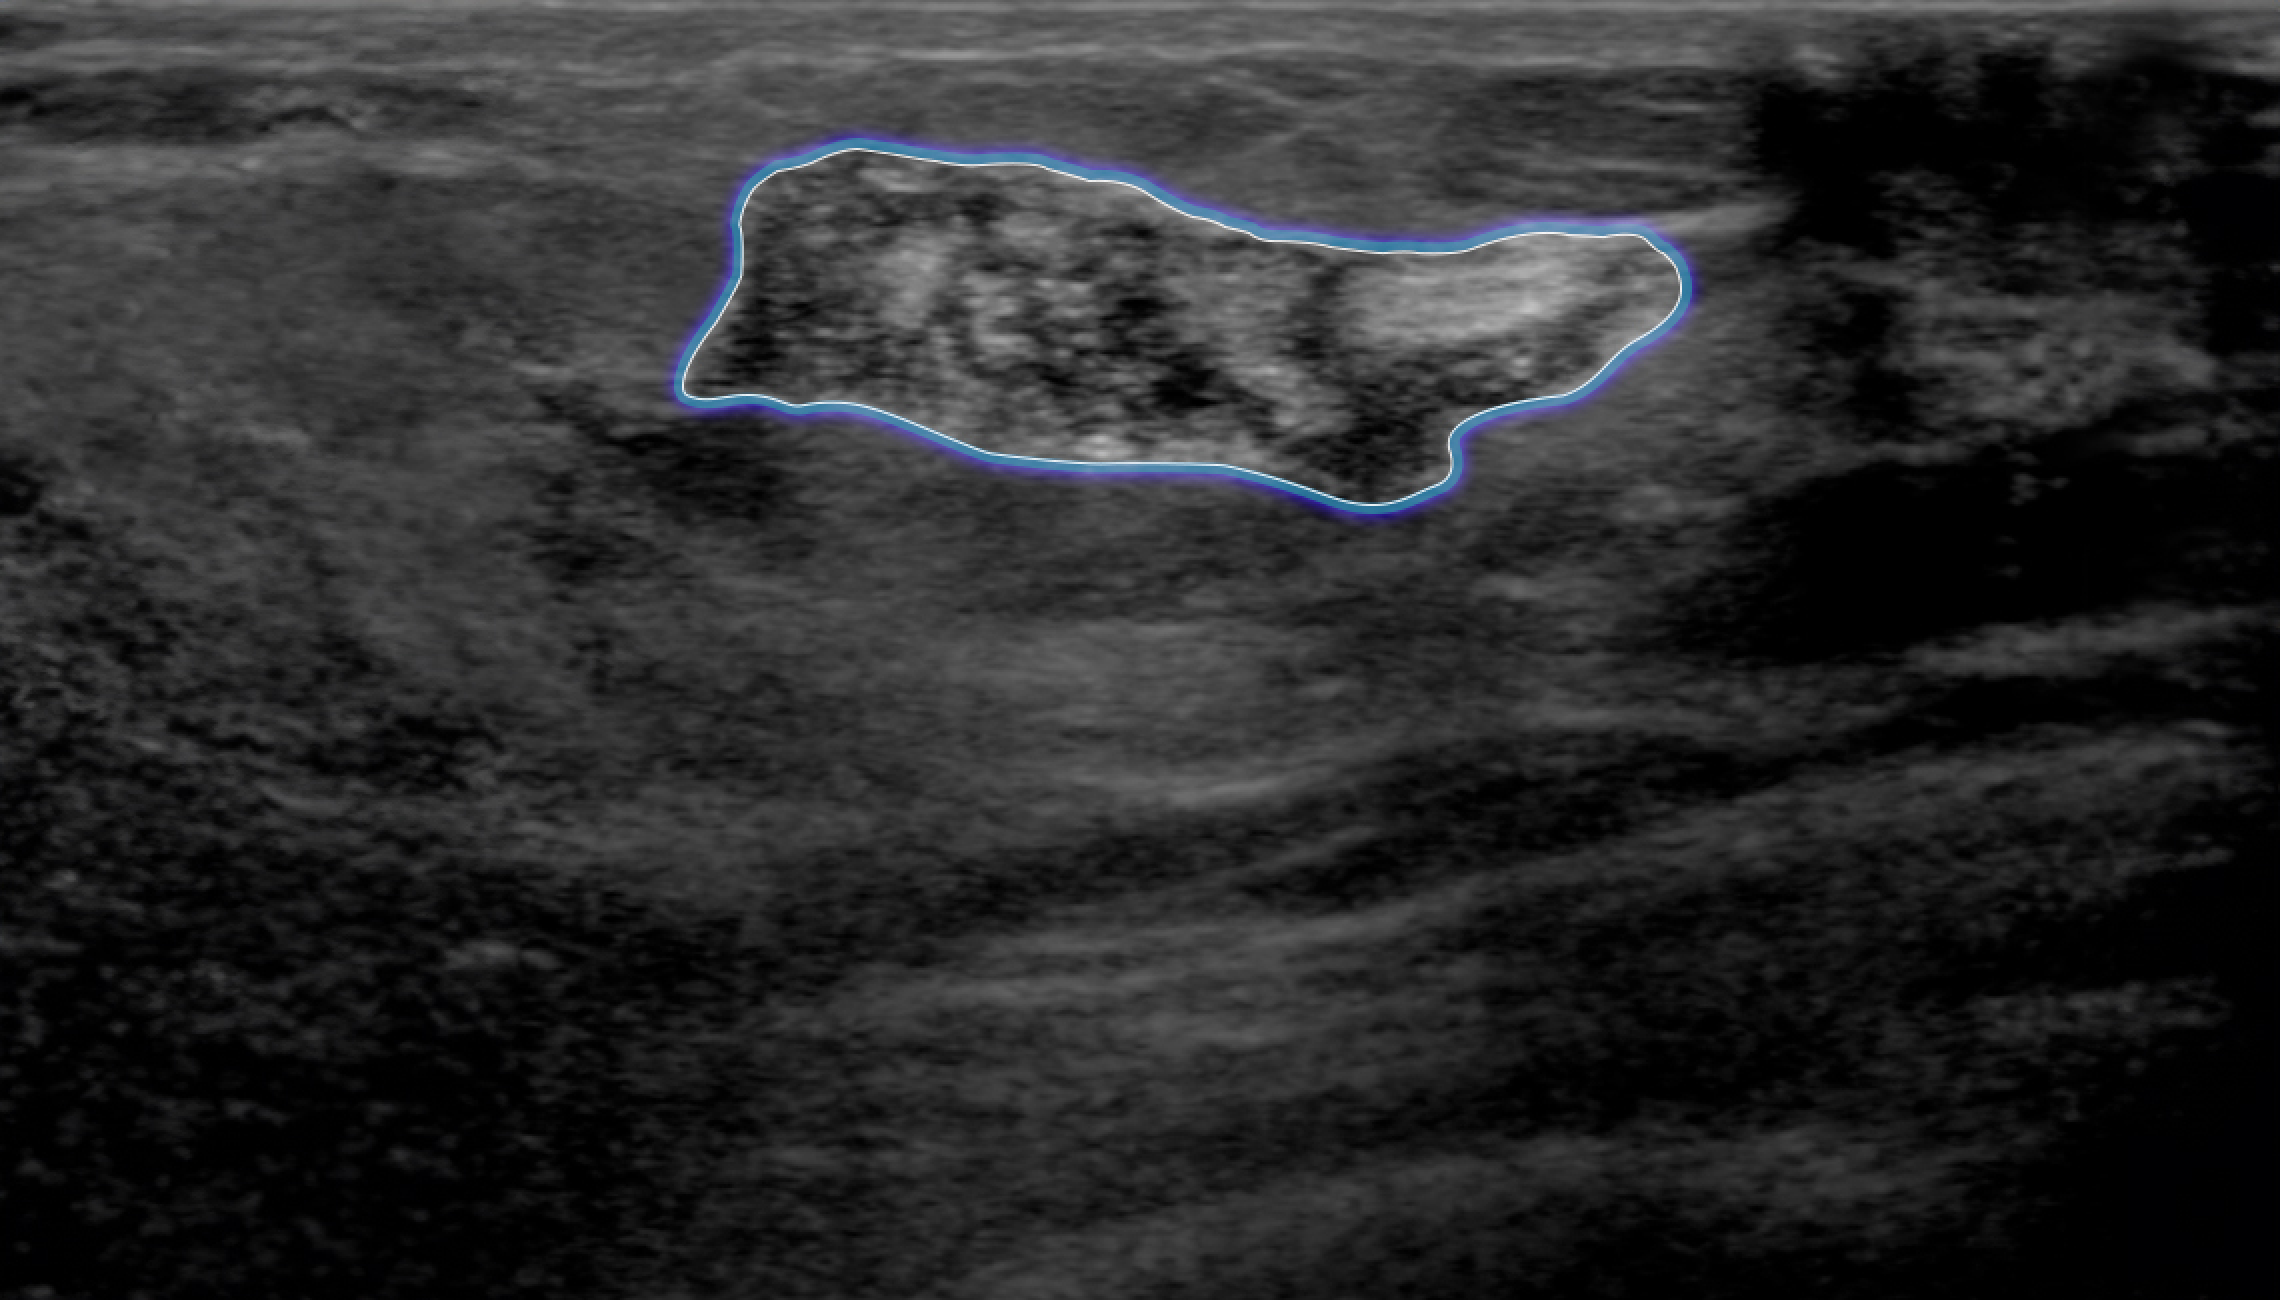

Automatic Detection of Abnormal Lesions

Automatically detects the locations of abnormal lesions in breast ultrasound images in real time.